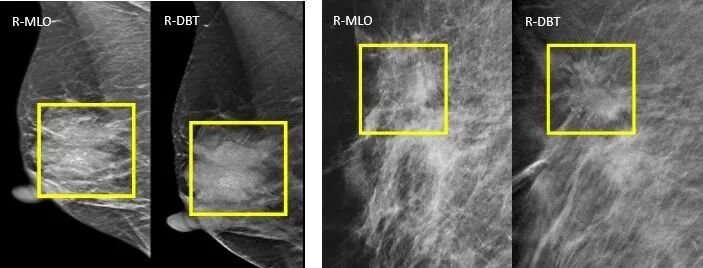

2.钙化的显示

病例4、病例5:MLO/DBT显示:肿块、形态、边缘、密度、大小、钙化显示显著优于MG,肿块边缘的分叶改变、细沙粒样征象显示更加明显。病理:乳腺浸润性导管癌。

3.结构扭曲的显示

病例6:纤维腺瘤手术史,MG结构扭曲不明确;DBT明确结构扭曲病灶。